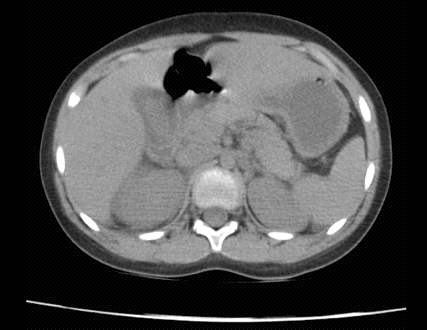

Mientras que dentro del estudio de TAC de abdomen realizado a 13 pacientes el principal hallazgo fue la presencia de líquido perivesicular en 4 (30,76%) de ellos (figura 1 y 2).

Figura 1. Tomografía de abdomen contrastada con evidencia de vesícula biliar distendida con pared gruesa y líquido perivesicular

Fuente: Departamento de Imágenes Hospital Dr. Roberto Gilbert Elizalde

Figura 2. Tomografía de abdomen contrastada en la que se visualiza vesícula biliar de forma y tamaño normal con líquido perivesicular